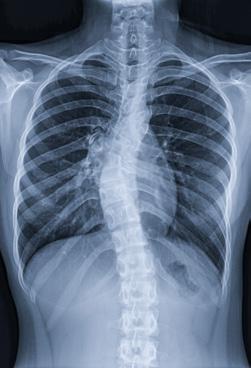

Consecințele scoliozei asupra respirației

Scolioza, o deformare tridimensională a coloanei vertebrale, este o afecțiune care nu afectează doar aspectul fizic al pacientului, ci poate avea implicații semnificative și asupra sănătății respiratorii. Scolioza are o prevalență variabilă între 0,3% și 15,3% în populația generală.

za este adesea asimptomatică și nu cauzează disconfort. Totuși, pe măsură ce coloana vertebrală suferă modificări în poziție și unghi, în funcție de localizarea curburii și de vârsta la care apar aceste schimbări, afecțiunea poate deveni evidentă prin simptome semnificative, inclusiv afectarea funcției respiratorii.

Scolioza congenitală este prezentă la naștere și rezultă din malformații vertebrale sau costale, adesea asociate cu tulburări sistemice. Pe de altă parte, scolioza idiopatică, care constituie aproximativ 85% din cazuri, nu are o cauză specifică identificată și apare în perioadele de creștere rapidă. Scolioza asociată cu sindroame cunoscute este adesea subclasificată drept „scolioză sindromică”.

Anomaliile funcției pulmonare devin detectabile în cazurile severe, în care riscul de insuficiență cardiorespiratorie este semnificativ crescut. În fazele incipiente, scolio-

Funcția pulmonară depinde în mare măsură de integritatea și dinamica complexă a scheletului toracic de susținere, a articulațiilor și a mușchilor. Modificările structurale cauzate de scolioză au un impact direct asupra mecanicii respiratorii. Deformarea coloanei vertebrale și a toracelui reduce complianța peretelui toracic, limitează mobilitatea coastelor și afectează forța musculaturii intercostale. Aceste schimbări conduc la o scădere a volumului pulmonar și determină compresia focală a căilor respiratorii. În special la copiii cu scolioză cu debut precoce, limitarea creșterii normale a toracelui și a plămânilor poate avea consecințe pe termen lung asupra dezvoltării respiratorii.

În practica clinică, pacienții cu scolioză pot dezvolta

un tipar de respirație rapidă și superficială, în încercarea de a compensa rigiditatea peretelui toracic. Această adaptare conduce la o scădere a capacității de efort și la apariția dispneei de efort, una dintre primele manifestări clinice ale scoliozei. Implicarea coloanei toracice (singură sau în combinație cu segmentul lombar) în scolioză este responsabilă pentru complicațiile respiratorii și cardiovasculare, iar distorsiunea cutiei toracice crește efortul respirator necesar.

Deși scolioza nu afectează direct mușchii respiratori, aceasta poate restricționa funcționarea lor. De exemplu, mușchii intercostali pot deveni „supraîntinși” sau pot avea dificultăți în a se extinde din cauza modificărilor dintre

Figura 1 Scolioza

spațiile intercostale, ceea ce le reduce eficiența, inclusiv capacitatea de expansiune a toracelui. Deformarea cutiei toracice determină un perete toracic (și, implicit, un sistem respirator) mult mai puțin elastic, ceea ce crește efortul necesar pentru respirație.

Datorită interconexiunilor complexe dintre coloana vertebrală, stern și coaste, mișcarea și rotația vertebrelor în cazul scoliozei au un impact semnificativ asupra formei toracelui, generând o latură convexă și una concavă. Pe lângă severitatea curbei coloanei vertebrale, vârsta pacientului joacă un rol în distribuția inegală a gazelor alveolare. Reducerea capacității de a efectua efort fizic la copiii cu scolioză nu se datorează doar scăderii capacității respiratorii, ci și diminuării abilității inimii de a se adapta la cerințele metabolice crescute. De asemenea, micșorarea diametrului anteroposterior al toracelui la acești copii determină o deplasare a inimii, afectând astfel funcționarea acesteia.

Complicațiile respiratorii asociate cu scolioza sunt variate și depind de vârsta la care debutează boala și de severitatea curbei. În cazurile severe de scolioză, există riscul apariției hipertensiunii pulmonare și a insuficienței respiratorii. Afectarea respiratorie care însoțește scolioza de cauză neuromusculară, poate varia considerabil între pacienți, chiar și în cadrul aceleiași boli.

Conexiunile dintre scolioză și afectarea respiratorie sunt complexe și au impact asupra sănătății pacienților. Recunoașterea acestor interacțiuni poate duce la dezvoltarea unor strategii de tratament care să abordeze nu doar deformarea coloanei vertebrale, ci și complicațiile respiratorii și cardiovasculare asociate.